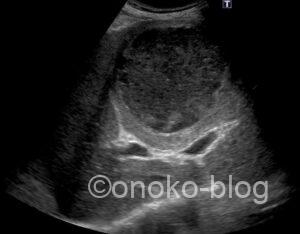

腹痛で来院された男性。

腸管かな~なにかあるかな~と思いながらプローブをあてると

おおっと(゚д゚)!

立派な充実性腫瘤ですね。測ると90㎜程ありました。

門脈も圧排されているように見えますよね。

腫瘤の内部エコーはカラードプラによる血流シグナルは認めず、

かつゼリーのようにふるふると動くのが確認できました。